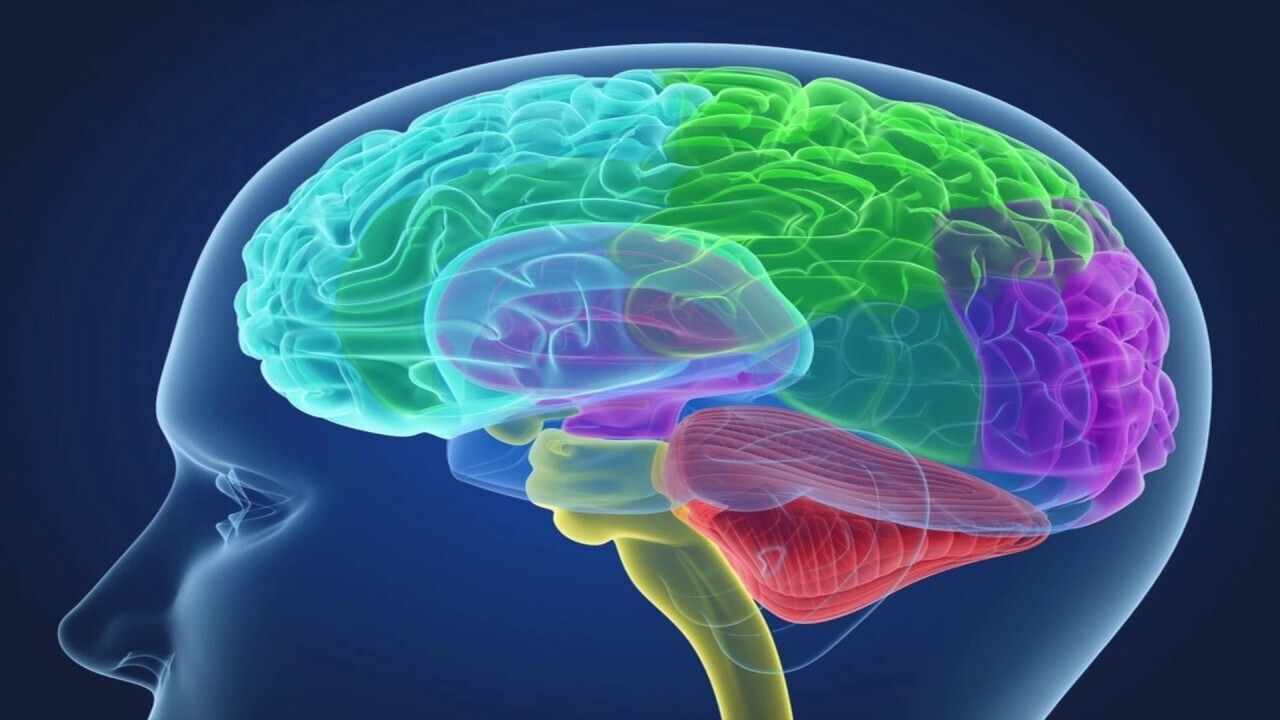

5. Мозг управляет всеми функциями нашего организма, от дыхания до пищеварения, от координации движений до выработки эмоций. Он также отвечает за наше сознание и мышление.